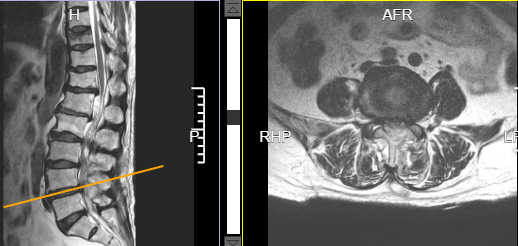

术后腰3/4椎管减压后狭窄解除